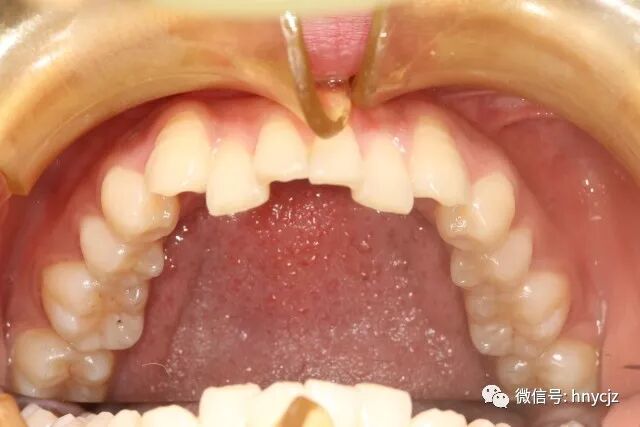

下牙下牙这颗牙齿是有够不整齐,借用崔医生的医生专业术语就是牙弓狭窄牙列拥挤。